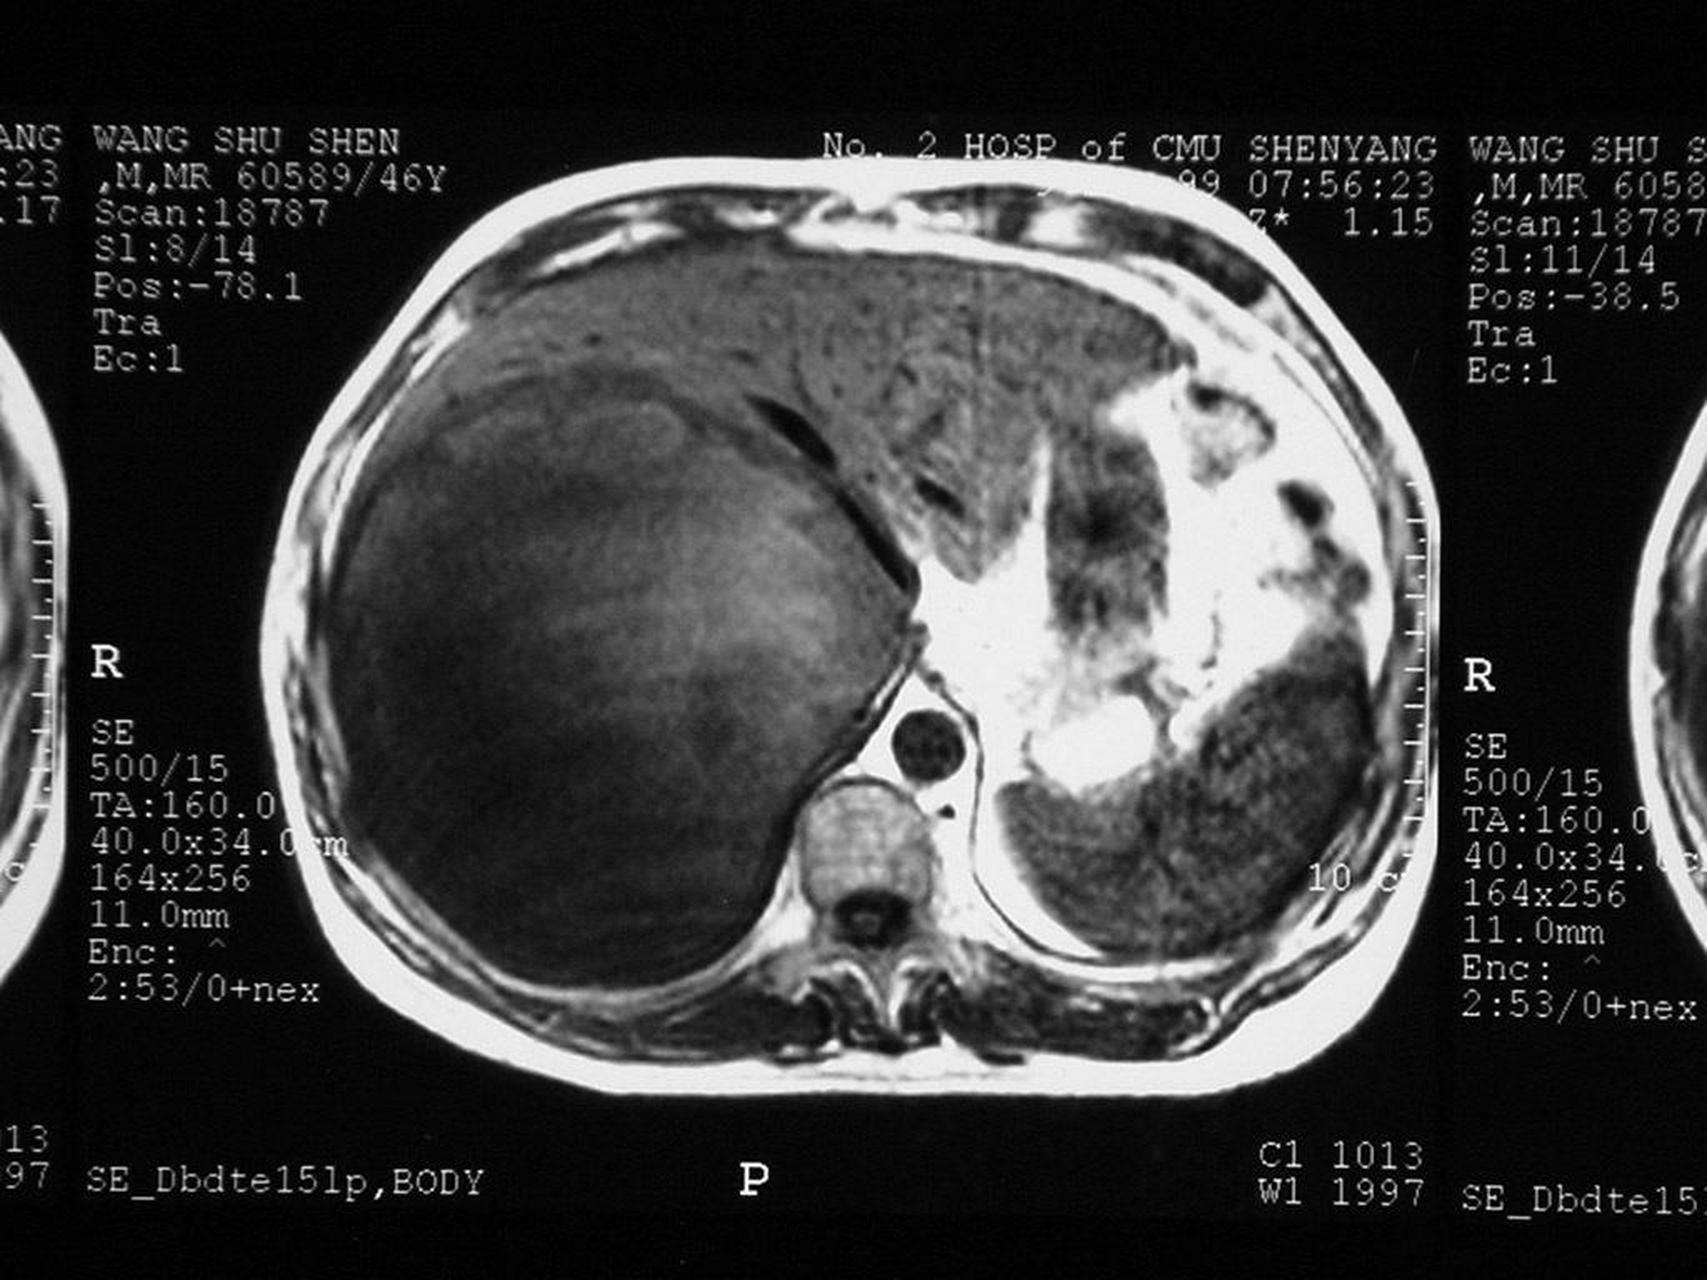

腹痛,腹胀1周,病人于1991年因直肠癌行手术治疗,如果拟诊为继发性肝癌